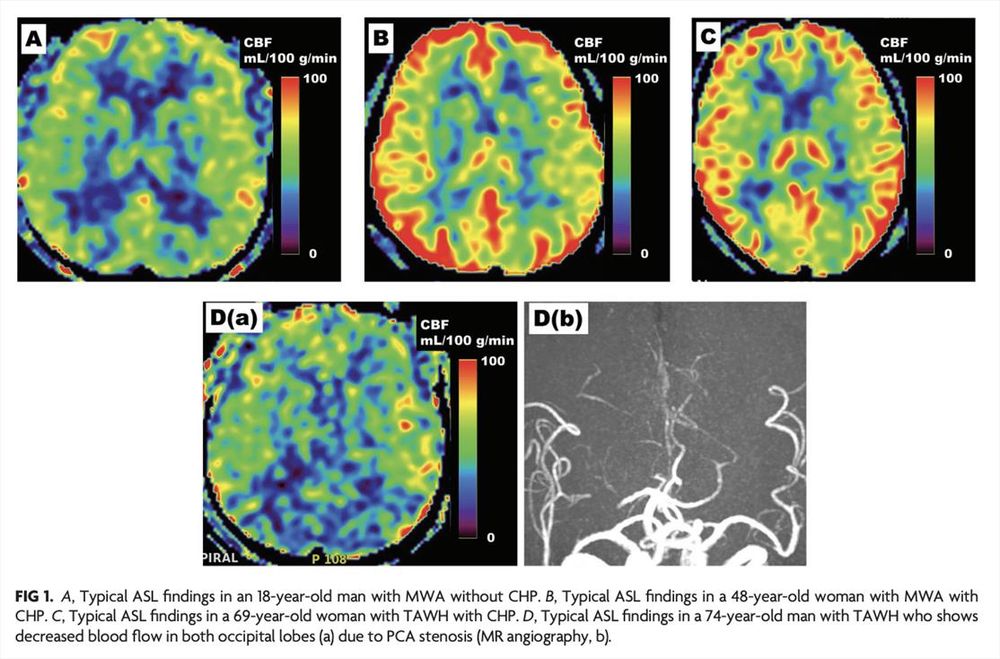

"Patients with Typical Aura without Headache with Cortical Hyperperfusion on Arterial Spin-Labeling MRI Have Clinical Features Similar to Those of Patients with Migraine with Aura"

doi.org/10.3174/ajnr...

#ASL #OpenAccess #FOAMed